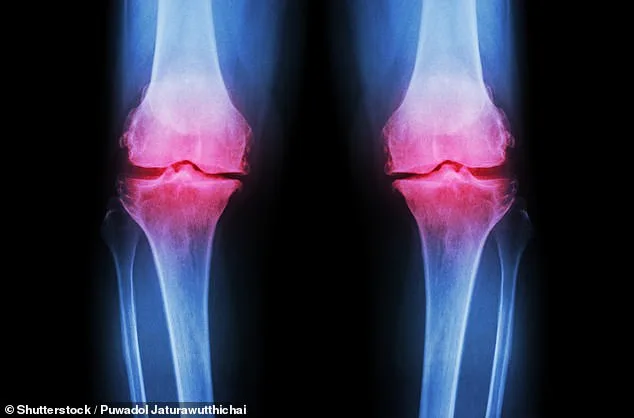

Osteoarthritis, the most prevalent form of arthritis in the UK, affects approximately 10 million people and is characterized by the progressive degradation of cartilage that cushions joints. As this protective tissue wears away, joints become painful, stiff, and increasingly difficult to move. Current treatments often rely on pain medications, which carry risks of side effects, or physiotherapy, which many patients struggle to maintain consistently. This study presents an alternative: a simple dietary intervention that could complement existing therapies and reduce reliance on pharmaceuticals.

Results revealed that both inulin and physiotherapy independently reduced knee pain over six weeks. However, inulin demonstrated additional benefits, including improved grip strength and reduced pain sensitivity—a critical factor for individuals with osteoarthritis, who often experience heightened sensitivity to even mild pressure or movement. The study also measured changes in GLP-1, a gut-derived hormone linked to muscle function and pain regulation, which increased significantly in the inulin group compared to controls.